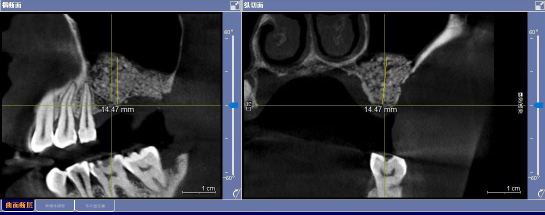

患者彭女士,左上第一磨牙缺失10余年,第二磨牙松动,无法进食。她关注到援藏专家在地区人民医院技术援助种植修复,就期盼通过种植手术修复缺失的牙齿。来自西安交通大学口腔医院的陈诚医生对其CT影像进行评估后,发现她的缺牙区骨垂直高度不足3mm,第二磨牙周围的牙槽骨也吸收到了上颌窦底,常规种植的希望渺茫。

联合应用CGF的上颌窦外提升植骨手术对技术要求极高,在操作过程中,还会伴有上颌窦底粘膜呼吸浮动,难度较大,需要医师有丰富的临床经验和过硬的专业技术水平,高海拔地区缺氧对操作的难度又增加不少。在陈诚的精细操作以及全体口腔科医护人员的全力协作下,手术历时1小时20分钟,完成了左上第一磨牙区的外提升植骨,完成了左上第二磨牙拔除术以及位点保存术。术后CBCT显示,患者左上第一磨牙区提升13mm以上,大幅度提升了骨量,为上颌后牙区进行牙种植提供了重要前提准备。